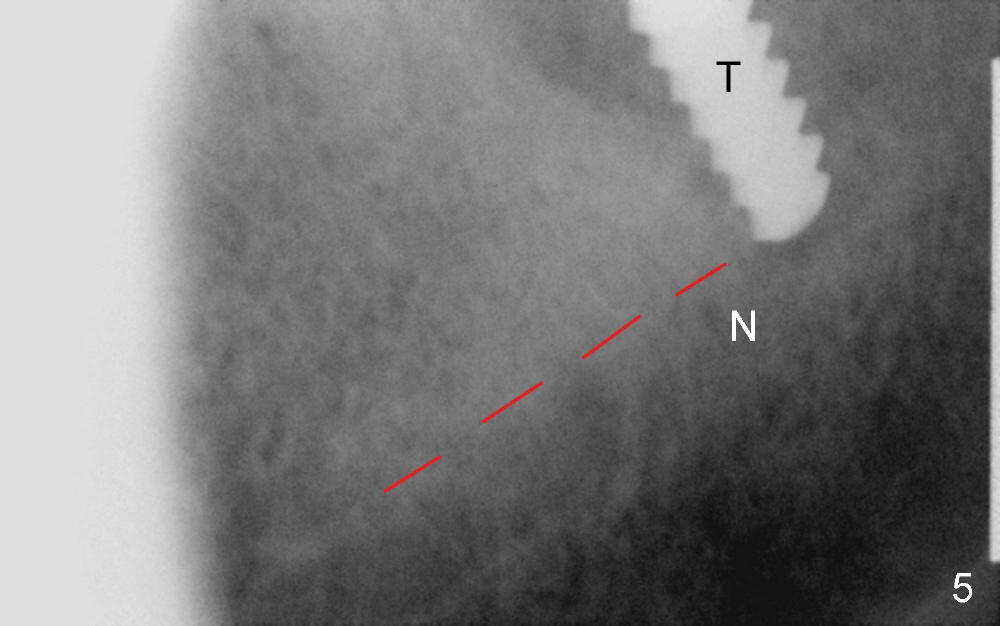

The lower left 2nd molar of a 45-year-old lady has perio-endo disease (Fig.1). The patient is not only very nervous, but also active in gag reflex. It is difficult to take good preop PA (Fig.1 *: ). Root canal therapy is performed. A relatively good PA is taken 1 year postop, again due to gap reflex (Fig.2). The tooth is still nonsalvageable (Fig.3). The last PA is taken 3.5 years before extraction and immediate implant. Infiltration anesthesia is administrated first. The patient experiences pain during early stage of osteotomy, but she does not report readily. Block anesthesia is added. Intraop PAs are taken with difficulty (Fig.4,5 with #1 sensor; 5 mm tap in place). Invasion of the inferior alveolar canal is not noted (Fig.5 dashed line). Oozing is a little more than expected. This is ignored. A 7x14 mm tapered implant is placed; the upper border of the inferior alveolar canal is not intact (Fig.6). Paresthesia area is defined next day (Fig.7). The implant is reversed for a few turns. Paresthesia area is reduced 19 days later (Fig.8). The implant is not stable. Follow up PAs are taken with difficulty (Fig.9-11). It appears that a shorter cylindrical implant is more appropriate for this case (Fig.11). The implant is stabilized with splinting with questionable result (Fig.12).